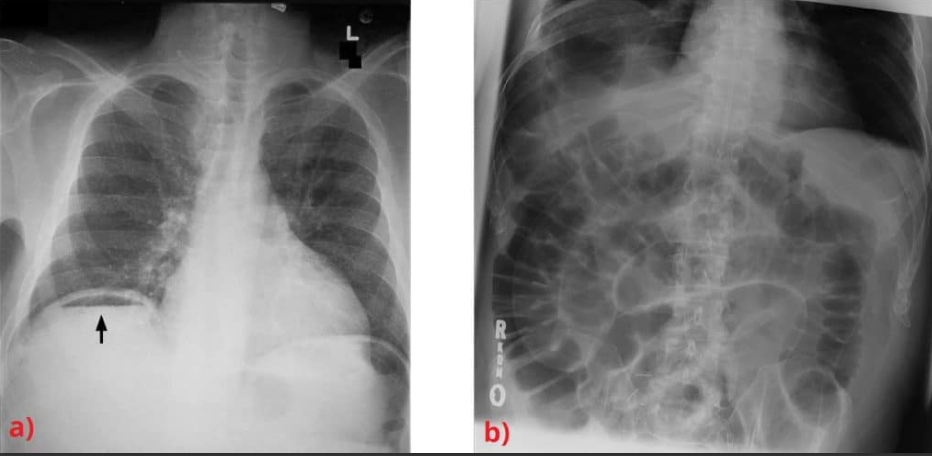

What do these images show?

Both evidence of pneumoperitoneum - can also get psoas sign

a- Pneumoperitoneum - air under diaphragm

b- Rigler’s sign (both sides of the bowel visible)